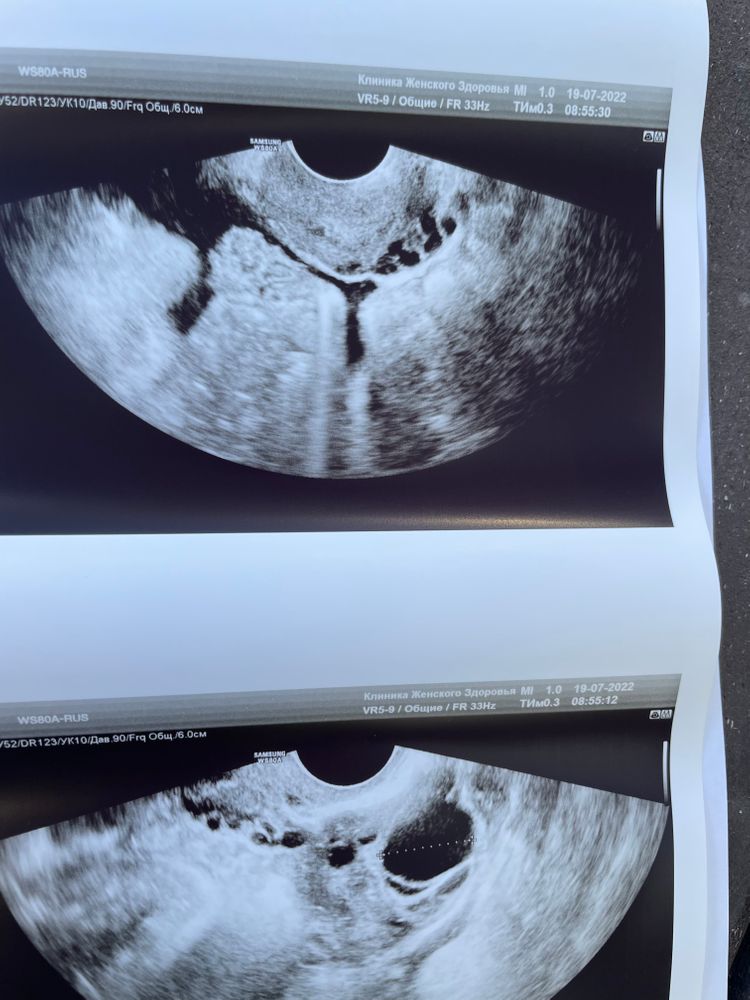

Фолликул или ЖТ?

По всем анализам спкя, сейчас 23 дц и созрел фолликул , сам!!!

сходила на узи. Вчера был 17,7.

Сегодня пришла на фолликулометрию и узистка сказала ,что овуляция видимо была ночью. Есть свободная жидкость. И ЖТ 18.5 .

Но меня терзают сомнения , что это все ещё фолликул.

Посмотрите пожалуйста фоточки 🙏🏻

Да, это фолликул.

От себя скажу, как врач УЗД - я больше не пошла бы к этому врачу, настройки изображения ужасны, а точнее они вообще отсутствуют. Как можно смотреть на такое - хз... От качества изображения, иногда очень многое зависит. Структуры тела матки не видно вообще. Контуры яичника еле видно

Фолликул. За день вырос на 1,5 мм.